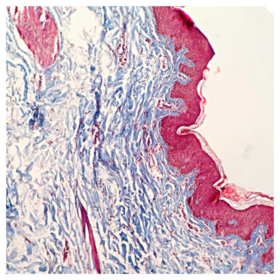

Láminas de Histología

Laboratorio de histología, Bibliografía Ross Pawlina 5ta Edición.